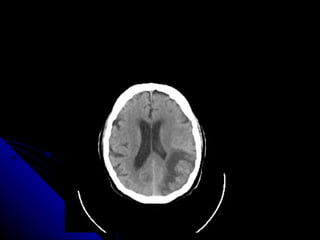

AFASIA GLOBAL Están gravemente afectadas tanto las funciones expresivas como receptivas del lenguaje.

LOCALIZACION Lesión extensa en el territorio de la arteria cerebral media izquierda, con afectación de las áreas frontotemporales y temporoparietales